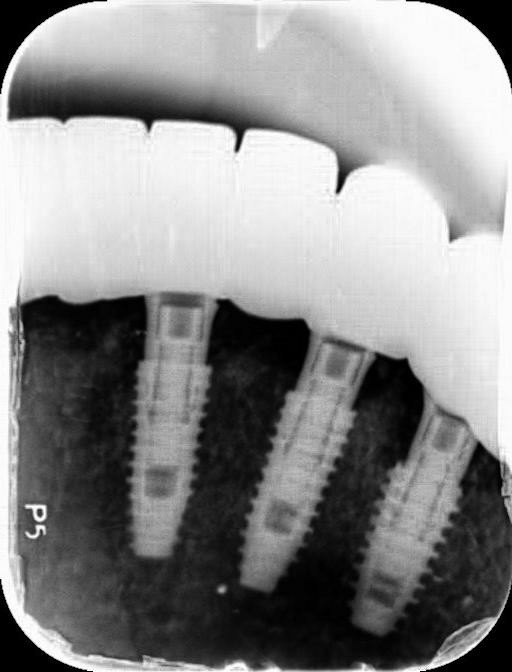

위 사진은 식립이 끝난 상태의 파노라마입니다.

잇몸 염증이 심한 만큼 많은 갯수의 임플란트를 식립하기 보다는 최대한 적은 갯수를 안정적으로 식립하여 구강 내 압력과 부담을 줄였습니다.

사진에서 살펴보실 수 있듯이 악당 6~8개 정도의 임플란트를 식립하고 그 위에 브릿지를 연결하는 방식으로 진행됩니다. 브릿지에 대한 설명은 이전의 게시글에서도 확인하실 수 있습니다.^^

구강 구조 및 신경의 위치 그리고 인접치와의 간격 등을 고려하여 식립된 걸 확인해볼 수 있는데요. 치조골과 상태 또한 안정적으로 결합되었습니다.